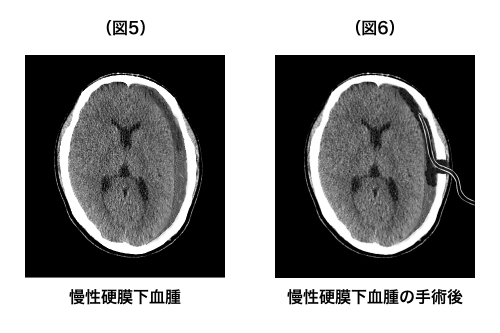

慢性硬膜下血腫の手術は頭蓋骨にに2cmくらいの穴を開けて、溜まった血液をそこから抜くためのチューブ(ドレーン)を差し込むというものです(図5~6:穿頭血腫ドレナージ術)。血溜まりを排出するためのチューブを一晩入れておき、翌日にチューブを抜くという流れです。これで8~9割の患者さんが完治します。

※(図5)灰色がかった三日月型の血腫が特徴的

※(図6)頭蓋骨の一部に穴が開き、そこから血抜きの管(ドレーン)を挿入している